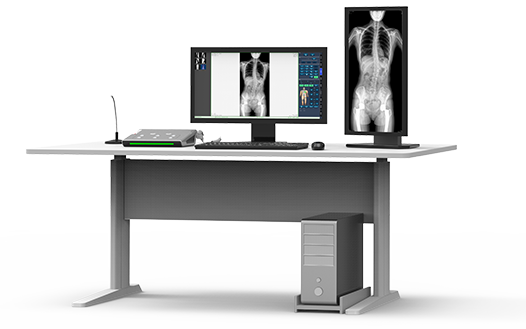

17"*34"有效视野,一次成像不拼接。相较于多张摄影再软件拼接的DR设备,PLX8600解决了拼接图像存在密度不均匀,拼接处图像配准和放大效应等问题,给临床带来了大视野影像解决方案,可一次性覆盖全脊柱或双下肢影像。

除常规静态摄影外,PLX8600大平板具备动态透视和点片功能,透视采集功能可支持大视野、多角度的可视化观察。通过可视化的动态影像,配合点片功能,能够很好的观察复杂部位病灶,有效的抓取关键帧,降低患者多次摄片的概率。如:全脊柱状态评估、长骨关节活动度、下肢静脉造影瓣膜功能评估、消化道功能评估、脊髓造影等更多大视野临床应用。